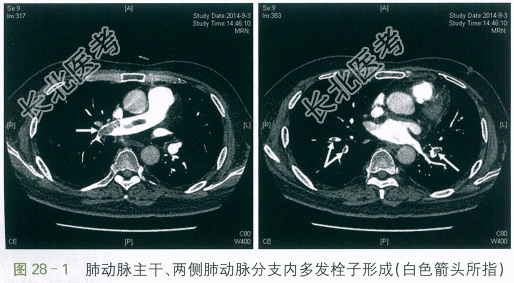

CT肺动脉造影示:肺动脉主干、两侧肺动脉分支内多发栓子形成(见图28-1)。

患者,男性,52岁。因"右下肢肿胀10余天,胸闷1周伴痰血"入院。患者10余天前出现右下肢肿胀,较左侧增粗,非凹陷性,表面皮肤无皮疹、破溃,未予重视。1周前自感胸闷,伴痰中带血3次,无发热、胸痛、呼吸困难、心悸等。2天前自感胸闷加重,遂至我院门诊就诊。查血常规:WBC9.93×109/L,Hb129g/L,PLT128×109/L。X线胸片示:两肺未见活动性病变。D-二聚体:15.78mg/L。进一步行CT肺动脉造影示:肺动脉主干、两侧肺动脉分支内多发栓子形成。遂予以收治入院。